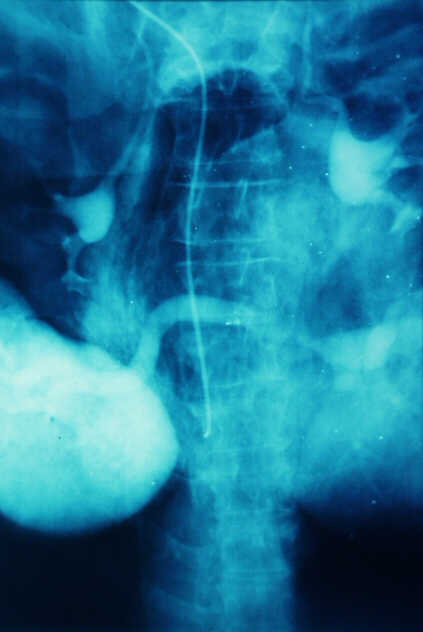

Pancreatic Head Mass: What Can Be Done?

Diagnosis: Angiography